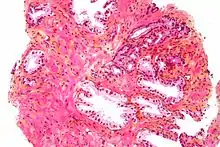

The prostate consists of glandular and connective tissue.[1] Tall column-shaped cells form the lining (the epithelium) of the glands.[1] These form one layer or may be pseudostratified.[3] The epithelium is highly variable and areas of low cuboidal or flat cells can also be present, with transitional epithelium in the outer regions of the longer ducts.[9] The glands are formed as many follicles, which in drain into canals and subsequently 12–20 main ducts, These in turn drain into the urethra as it passes through the prostate.[3] There are also a small amount of flat cells, which sit next to the basement membranes of glands, and act as stem cells.[1]

The connective tissue of the prostate is made up of fibrous tissue and smooth muscle.[1] The fibrous tissue separates the gland into lobules.[1] It also sits between the glands and is composed of randomly orientated smooth-muscle bundles that are continuous with the bladder.[10]

Over time, thickened secretions called corpora amylacea accumulate in the gland.[1]

Microscopic glands of the prostate

Microscopic glands of the prostate